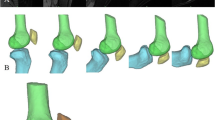

The data were imported in MATLAB (The MathWorks® Inc., Natick, MA, USA) and processed according to the following workflow: using the tactile scanner, the surgeons registered points of important anatomical landmarks for the establishment of the reference system and manually sampled the anterior femoral cortex intraoperatively by using the pointing device (Fig. 2a). The sampled point data were imported in MATLAB as a text file from which 3D location coordinates were retrieved to reconstruct the surface of the anterior cortex by triangulation from the intraoperatively sampled points. The space between the points was represented by linear interpolation. The surface was therefore generated as a polygon model where the triangles were represented by the nodes as their corners (Fig. 2b, c).

Workflow for the surface reconstruction of the femoral anterior cortex by means of the intraoperatively recorded point cloud. Using a commercially available navigation system (Precision Knee Navigation software v4.0, Stryker Orthopaedics, Mahwah, NJ, USA) with the tactile scanner (a), the anterior cortex was sampled with emphasis on the trochlear groove before and after total knee arthroplasty. The recorded point clouds (b) served as the basis for the surface reconstruction using an in-house code (c)

By extending our MATLAB code, the geometric parameter sets for the evaluation of SH, medCH, and latCH could be automatically extracted (Fig. 3). To do so, a reference plane containing the lateral and medial epicondylar points, the femoral head center, and the lateral and medial epicondyles defining the TEA was established. Then, a second plane, the so-called cutting plane was defined as being perpendicular to the reference plane and comprising the TEA. Accordingly, any rotational displacement between this cutting plane and the reference plane produces a cutting angle (θ), where θ = 0° corresponds to the state where the cutting plane and reference plane are perpendicular (Fig. 3a, b). Cutting planes were generated incrementally in 1° steps for angles ranging from θ = −45° (cranial) to θ = +45° (caudal). Each of the resulting cross-sections contained the contour of the reconstructed femoral anterior cortex, which was analyzed in terms of the parameters of interest: SH, medCH, and latCH (Fig. 3c).

The cutting contour was represented by points that were interpolated to a continuous curve. Smoothing of the surface, search for local extrema, and the deepest point of the trochlear sulcus, the SH, as well as the medCH and latCH of this surface and the respective cutting contours were performed. All values were evaluated about the established Cartesian system defined from the anatomic landmarks (Fig. 3b). For each cross-section, the geometric parameters were determined automatically using the previously described MATLAB code. Figure 3 shows a schematic description of the evaluation of the trochlear groove parameters.

Process of the automated evaluation of geometric trochlear groove parameters. Starting from the reference plane (RP) referring to θ = −45° cranial, the cutting plane rotated around the transepicondylar axis (TEA) to θ = +45° caudal in 1° increments (a). The key parameters sulcus height (SH), medial condyle height (medCH) and lateral condyle height (latCH) were extracted from the computed cutting contour using a custom MATLAB program (b). The key parameters were determined for each angular increment of the cutting plane and the native as well as the artificial anterior cortex geometry (c)